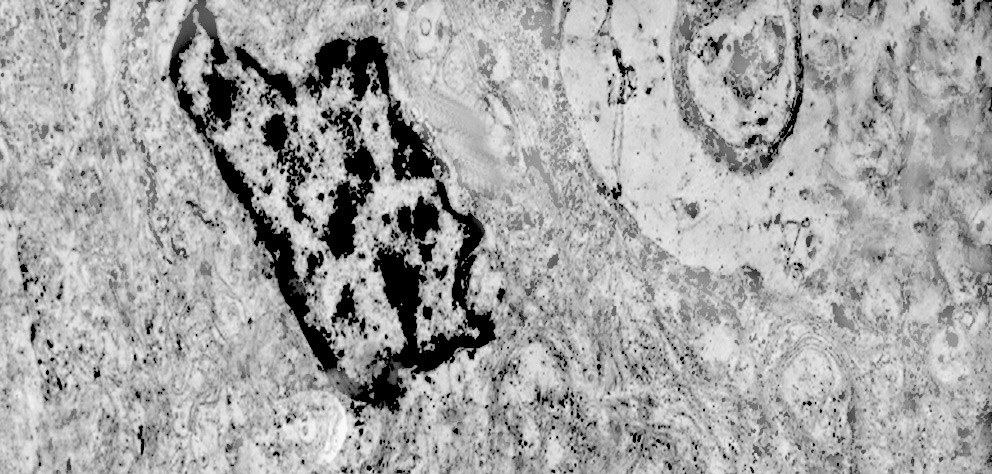

Alcune cellule meningoteliali sono sedi, sopratutto a livello delle fasce periferiche, di ampie vescicole, di forma irregolare le quali sono demarcate da una membrana a mono-strato; gli spazi di queste vescicole sono in buona parte occupati da materiale amorfo, da frammenti filamentosi e da organuli intracitoplasmatici,tutto sottoposto a degradazione.

E’ possibile anche il reperto di elementi cellulari aventi il citoplasma occupato da ampie vescicole,delimitate da una membrana a monostrato, le quali sono ricolme di materiale amorfo,da strutture granulo-filamentose o da frammenti di organuli.